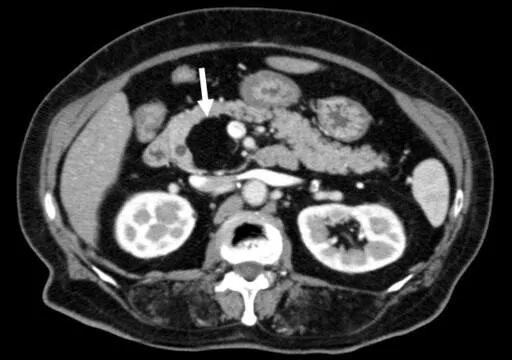

Липоматоз поджелудочной лечение лекарствами